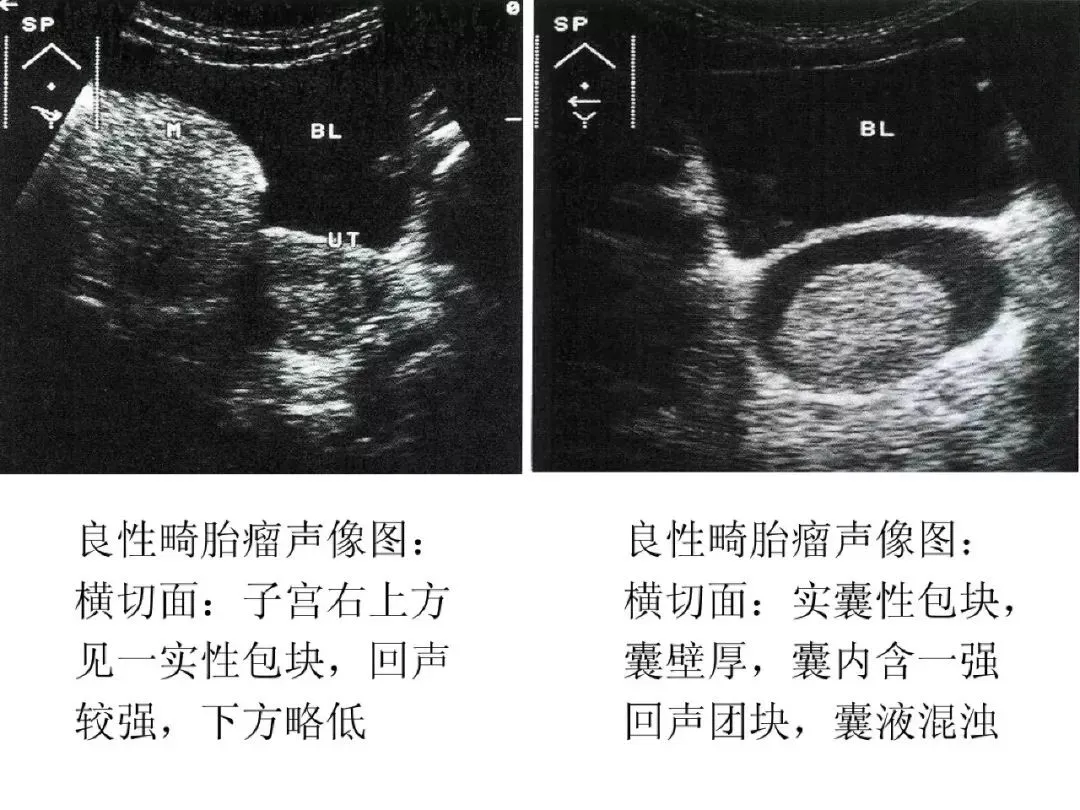

●良性畸胎瘤超声特点:圆形或椭圆形,多为单侧;壁厚,清晰或不清;囊内显示飘浮光点,如面团征、发团征、脂液分层征;内可显示强回声光团、光带。

●声像图特征:肿瘤较大,呈圆形、椭圆形或欠规则;瘤壁厚;内部回声较复杂,可出现脂液分层,强回声光团或低回声实性区;内部血流较丰富。